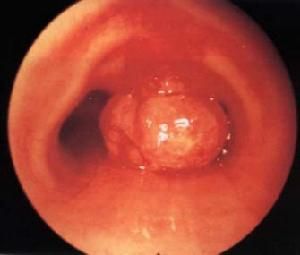

原發性氣管良性腫瘤種類多,形態不一。在多數腫瘤生長緩慢。表面光滑,黏膜完整,常有瘤蒂,不發生轉移。但如切除不徹底易復發。乳頭狀瘤多發生於氣管膜部,突入氣管腔底部,常有細蒂,大小自數毫米至2cm。有時為多發性,表面呈疣狀,質軟而脆易脫落,破裂時出血。

鱗癌和小細胞癌以管壁浸潤性生長為主,質脆,觸之易出血,發生於支氣管內的幾率高於氣管內。 黏液表皮樣癌發生於主支氣管內,較少見。癌腫呈侵蝕性生長,但大多數生長緩慢,病程較長。乳頭狀瘤起源於黏膜上皮組織,為良性腫瘤,常發生於支氣管近端,入支氣管腔內,呈簇狀或單個息肉狀,有短蒂附著於支氣管壁的黏膜或黏膜下層,表面呈白色顆粒狀,質脆易碎。類癌起源於支氣管黏膜的具有神經內分泌功能的Kulchitsky細胞,與腺樣囊性癌不同,好發於主支氣管和遠段支氣管。

氣管腫瘤氣管X線斷層攝片檢查可顯示腫瘤的位置範圍和氣管腔狹窄的程度。氣管碘油造影檢查對診斷氣管腫瘤也很有價值,但有加重氣管梗阻的危險,僅適用於梗阻程度較輕的病例。內窺鏡檢查可直接窺見腫瘤,了解腫瘤的部位、大小、表面形態和活動度,並可採取組織作病理切片檢查確定腫瘤的性質和類型。但對於黏膜完整且含有豐富血管的良性腫瘤,不宜常規作活組織檢查,以免引致大量出血。